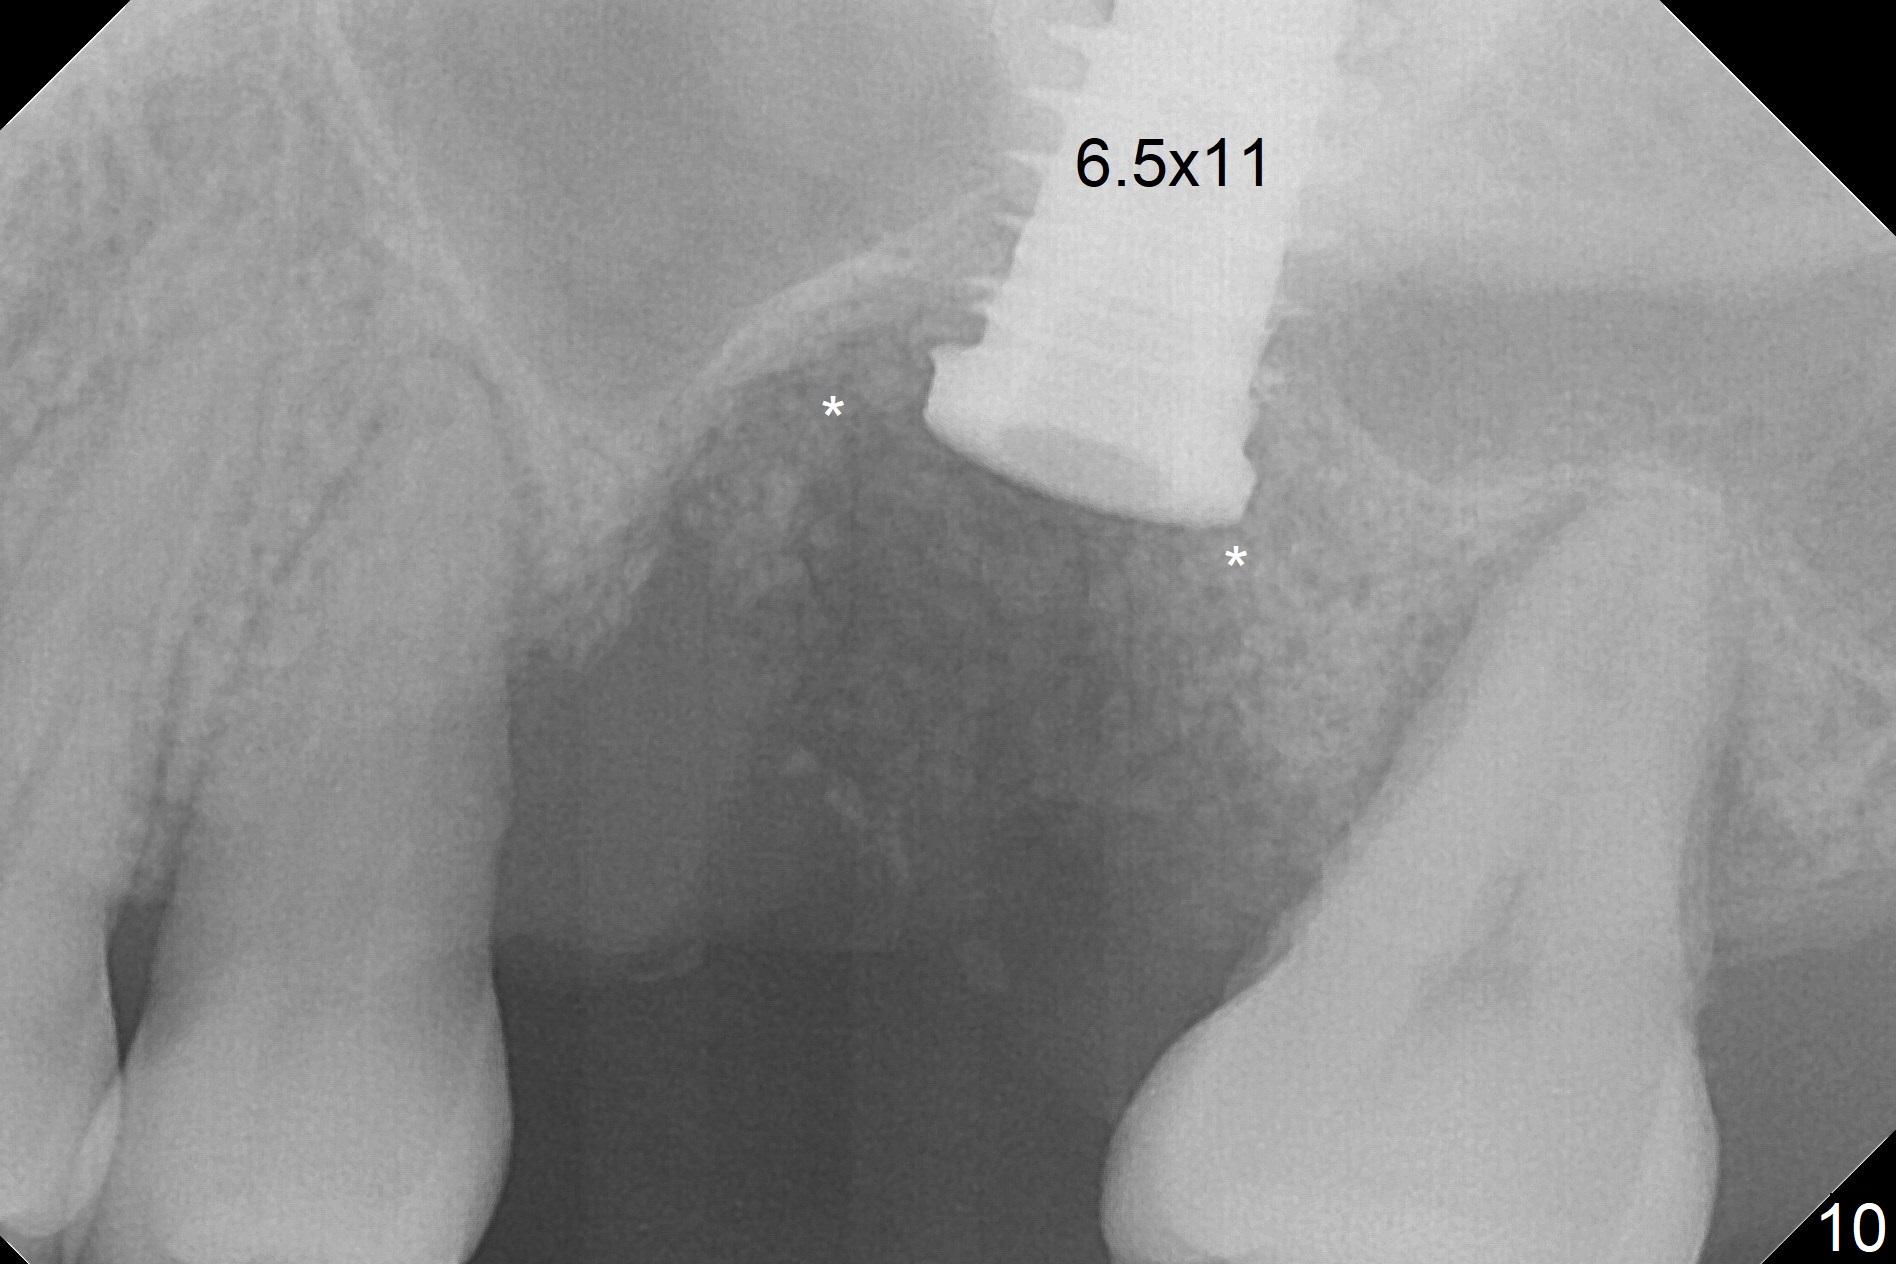

When the displaced tooth #14 (Fig.1) with palatal gingival recession (Fig.2) is extracted, the buccal plate is low, while the palatal one is lost.  Osteotomy is initiated in the bottom of the large socket with Marking Drill.  The bone turns bluish, suggesting thin bone (in fact less than 1 mm as well as low density).  Magic Sinus Lifter (Fig.3 *, Fig.4 blue area) is used for sinus lift (Fig.4 (red curved line: lifted sinus membrane; grey area: a portion of the lifted sinus floor), followed by insertion of a piece of PRF plug and Vanilla bone graft for sinus lift.  The osteotomy is enlarged lightly with 4.8 mm Magic Drill (compare black strips between Fig.4,5).  A 5x9 mm dummy implant (Fig.5 green) is dislodged into the sinus.  The lifted sinus membrane holds the implant in place.  The black thin strip in Fig.5 and black circle in Fig.6a (occlusal view) represents the osteotomy.  After increase in the osteotomy with Lindamann bur (Fig.6b red circle), the implant (Fig.6c green) is retrieved with endodontic forceps (Fig.6c two blue dots (beaks of the forceps); Fig.7,8).  With the enlarged osteotomy (Fig.6d), a 6x9 mm dummy implant is placed deep (Fig.9).  The definitive implant is 6.5x11 mm with insertion torque ~ 15 Ncm (Fig.10).  With placement of a healing screw and further placement of allograft (Fig.11 *), the socket is closed with PRF membrane and collagen plug (Fig.12).

Questions for Dr. Wang: Can we remove the coronal portion of the bone (Fig.13) and back up the implant (Fig.14 arrow) 4-5 months postop for easy restoration?  If it is not a good option, can we produce pair abutments with 5 and 7 mm cuffs?